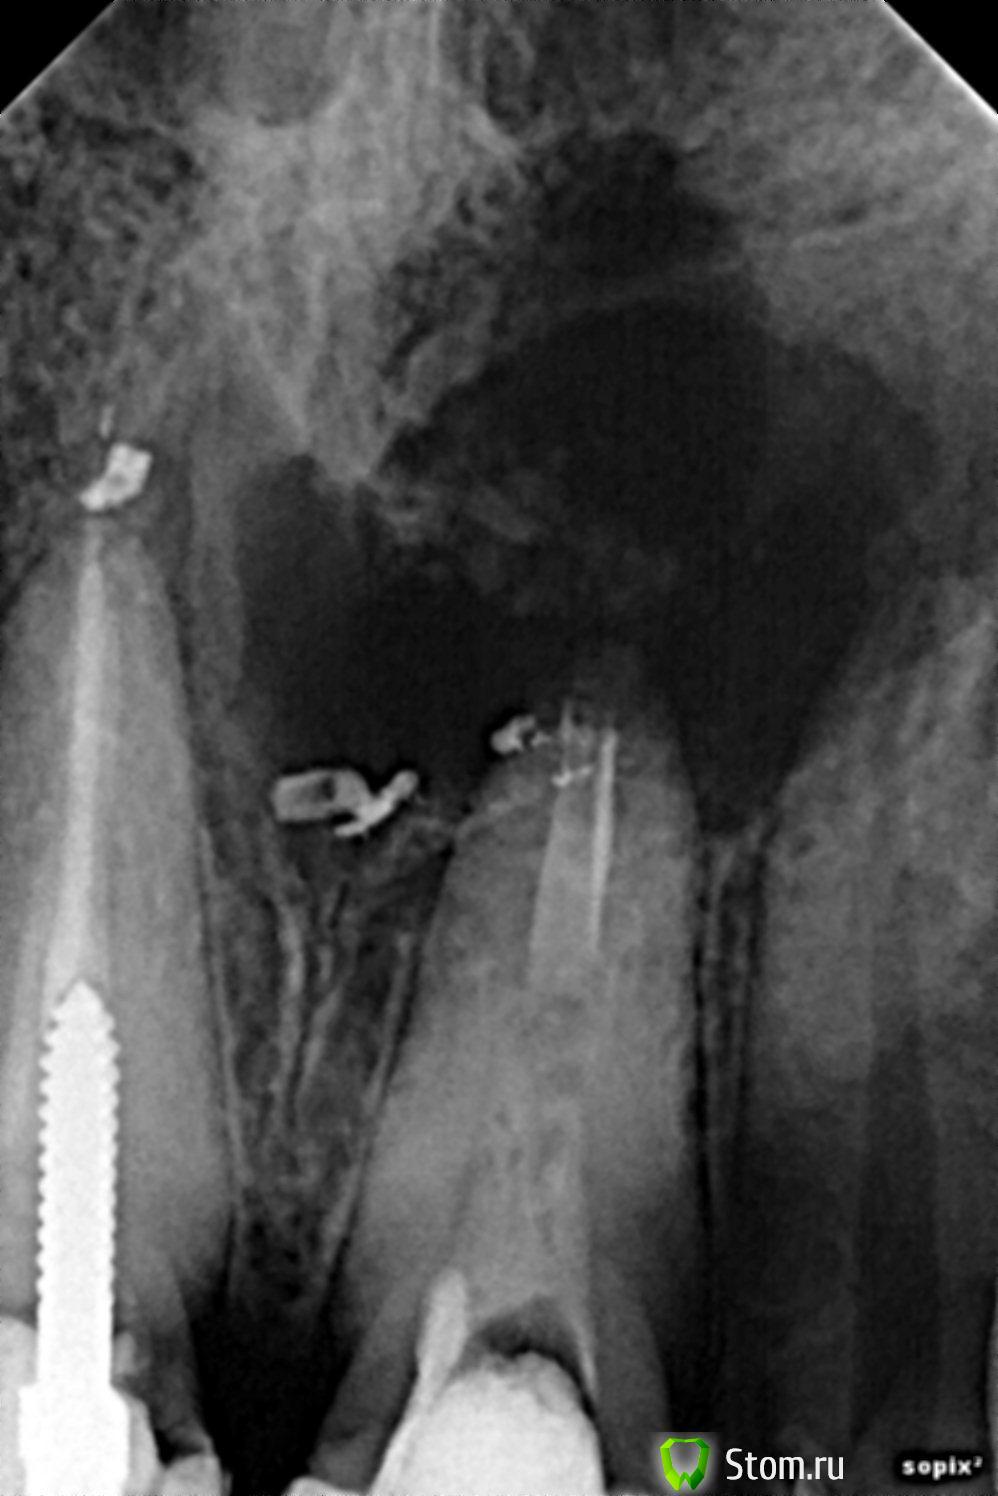

aleksisAG Опубликовано 7 апреля, 2012 Поделиться Опубликовано 7 апреля, 2012 Пациент 30 лет,женщина,6 месяцев 21 под "каласептом",свищь Ссылка на комментарий

red_butler Опубликовано 9 апреля, 2012 Поделиться Опубликовано 9 апреля, 2012 Проведите ЭОД на 2.2 - по снимкам он в дефекте. Далее КТ. Затем скорее всего постоянное эндо 2.2 2.1 и цистэктомия. Ссылка на комментарий

aleksisAG Опубликовано 15 апреля, 2012 Автор Поделиться Опубликовано 15 апреля, 2012 пациентка обратилась после эндо-,6 мес.на каласепте,если провести депофорез с последующей пломбировкой,сделать КТ,цистэктомию.Есть ли смысл 2.1 2.2 сохранять,кто работал с изиграфт,работает ли он вообще Ссылка на комментарий

Sashkatzar Опубликовано 16 апреля, 2012 Поделиться Опубликовано 16 апреля, 2012 22 на витальность,постоянное эндо и РВК Ссылка на комментарий